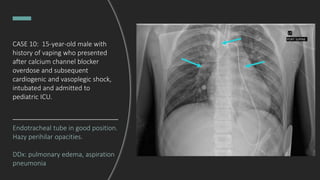

CASE 10: 15-year-old male with

history of vaping who presented

after calcium channel blocker

overdose and subsequent

cardiogenic and vasoplegic shock,

intubated and admitted to

pediatric ICU.

What do you see?

Endotracheal tube in good position.

Hazy perihilar opacities.

DDx: pulmonary edema, aspiration

pneumonia